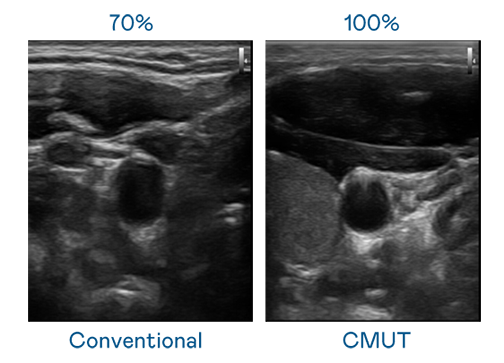

CMUT 技术是一种用电容式微机电元件来产生超音波讯号的技术。与传统 PZT 压电式技术相比,CMUT 频宽增加 30%,更宽频的超音波讯号让影像解析度大幅提升,是实现高影像品质医疗超音波扫描、促进精准医疗发展的关键技术。

大频宽带来超清晰影像

超音波影像的解析度高低,首先取决于探头能发出的讯号频宽。鉴黄师app免费安装 CMUT 可提供高清晰的超音波讯号,提供高频宽、高灵敏度、影像纹理细节更高的超音波影像,协助医护人员缩短影像判读时间及利用精准的医疗影像进行诊断。